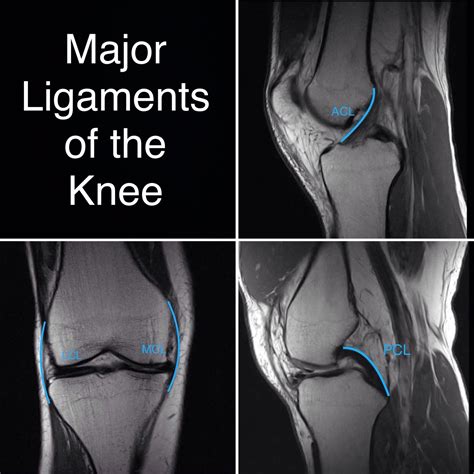

Interpreting a Knee Normal MRI involves looking at various structures within the knee to ensure they appear healthy. Key components to examine include:

• Bones: The femur, tibia, and patella should show no signs of fractures, tumors, or other abnormalities.

• Cartilage: The articular cartilage should be smooth and intact, with no signs of wear or tear.

• Ligaments: The anterior cruciate ligament (ACL), posterior cruciate ligament (PCL), medial collateral ligament (MCL), and lateral collateral ligament (LCL) should appear strong and unbroken.

• Tendons: The patellar tendon and other tendons should be intact and free of inflammation.

• Menisci: The medial and lateral menisci should be smooth and evenly distributed, with no signs of tears or degeneration.

Here is a simplified table of what to look for in a normal knee MRI:

Structure Normal Appearance

Bones No fractures, tumors, or other abnormalities

Cartilage Smooth and intact

Ligaments Strong and unbroken

Tendons Intact and free of inflammation

Menisci Smooth and evenly distributed

• Ligament Tears: Tears in the ACL, PCL, MCL, or LCL can be clearly seen on an MRI.